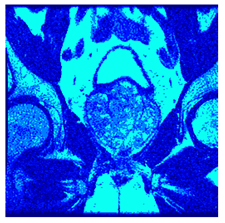

| Image | nt = 3 | nt = 4 | nt = 5 | nt = 8 |

|---|---|---|---|---|

| 1 | ![]() | ![]() | ![]() | ![]() |

| 2 | ![]() | ![]() | ![]() | ![]() |

| 3 | ![]() | ![]() | ![]() | ![]() |

| 4 | ![]() | ![]() | ![]() | ![]() |

| 5 | ![]() | ![]() | ![]() | ![]() |

| 6 | ![]() | ![]() | ![]() | ![]() |

| 7 | ![]() | ![]() | ![]() | ![]() |

| 8 | ![]() | ![]() | ![]() | ![]() |

| 9 | ![]() | ![]() | ![]() | ![]() |

| 10 | ![]() | ![]() | ![]() | ![]() |

| 11 | ![]() | ![]() | ![]() | ![]() |